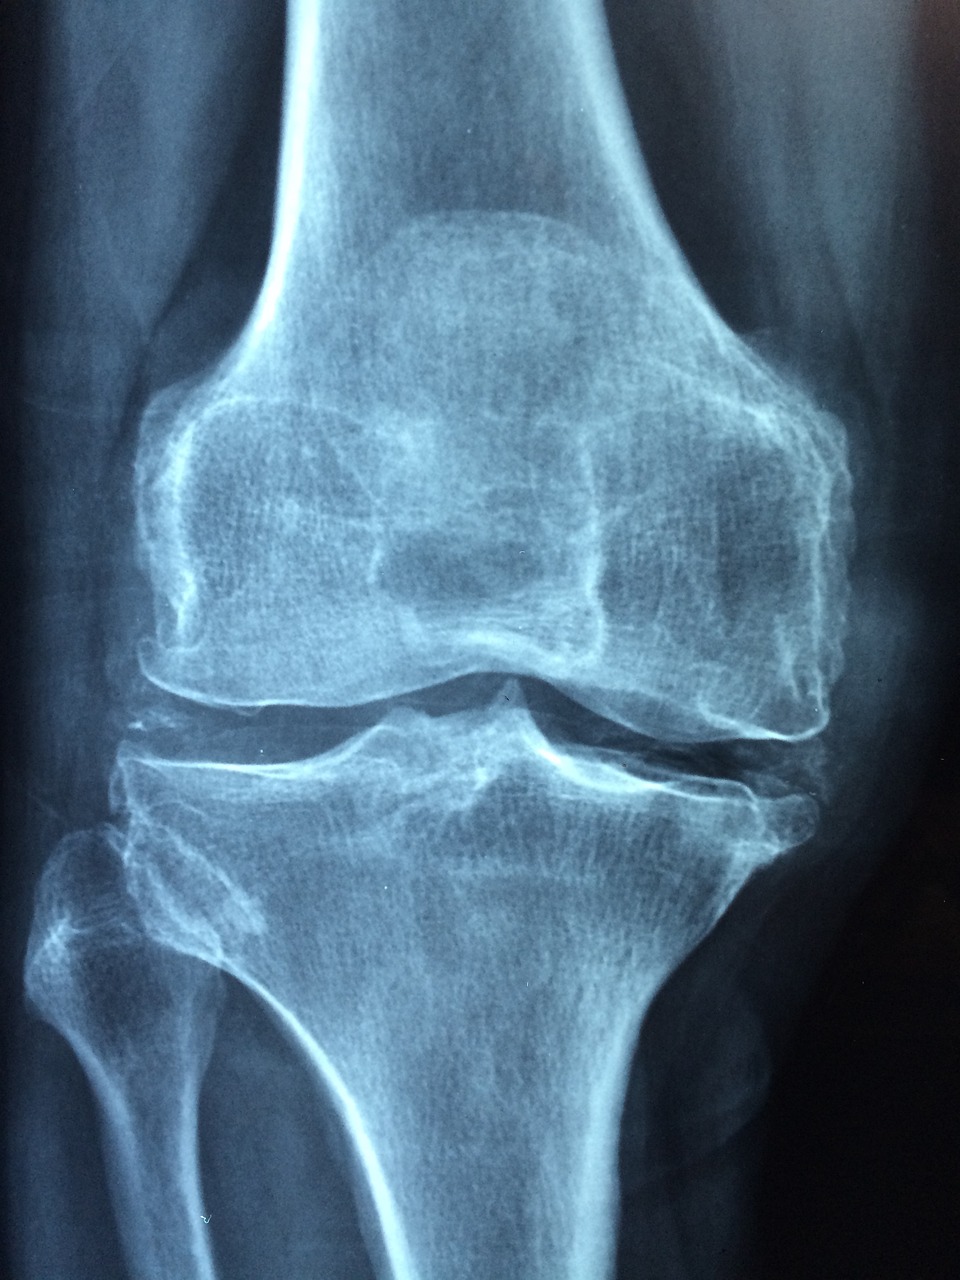

그러나 나이가 들면서 뼈의 밀도가 감소하고 골다공증이 발생할 수 있습니다.

골다공증은 뼈가 연약해지고 쉽게 골절이 발생하는 질환으로, 많은 사람들에게 영향을 미치고 있습니다.